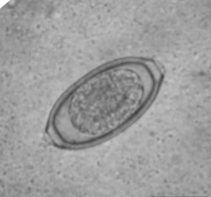

Dioctophyma renale

“giant kidney worm” of dogs, mink, raccoons, and humans

where does Dioctophyma renale live in the body of host

infects the right kidney.

symptoms of Dioctophyma renale

kidney/abdominal pain, enlargement, hematuria, proteinuria, lethargy, weight loss, can destroy entire contents of kidney, just leaving a “shell”

what lifecycle does Dioctophyma renale have

indirect with 2 aquatic intermediate hosts (worm and frog or fish)